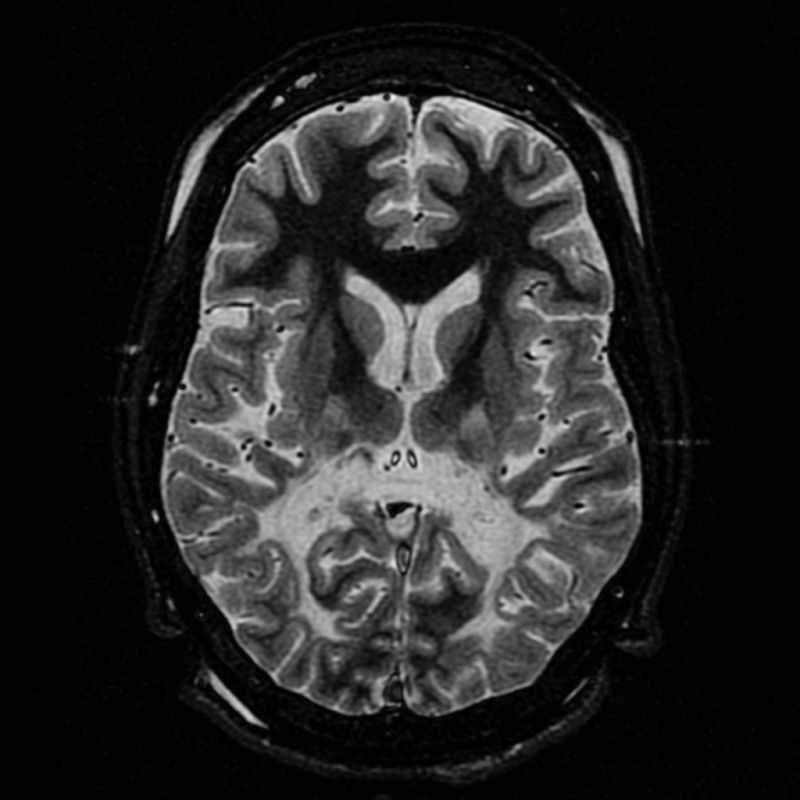

Заболяване като адренолевкодистрофия може да бъде предизвикателство за всяка фармацефтична компания. Въпросното е свързано с X хромозома и представлява натрупване на мастна киселина върху определени ензими и сериозно нарушава миелиновата обвивка на нервите. В последствие пациентът може да припада или да става хиперактивен за секунди. Заболяването затруднява говореното, слушането и комуникацията като цяло.

Колкото повече напредва, толкова по-сериозни са и шансовете пациентът да изпадне във вегетативен стадий. И до днес медицината не може да даде красноречив отговор какво може да е правилното лечение. Предложенията често са трансплантанция на стволови клетки, лечение на бъбречната жлеза със стероиди и други по-леки терапии, които облекчават болките, но нищо друго.